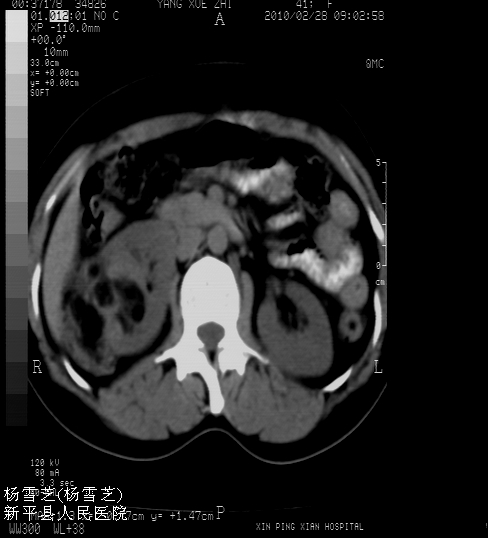

标题: CT24780:女 41岁 右肾多发低密度占位性病灶 [打印本页]

女 41岁 超声检查:右肾多发实质性包块,性质待查(提示:错构瘤或其它病变),临床病史不详。